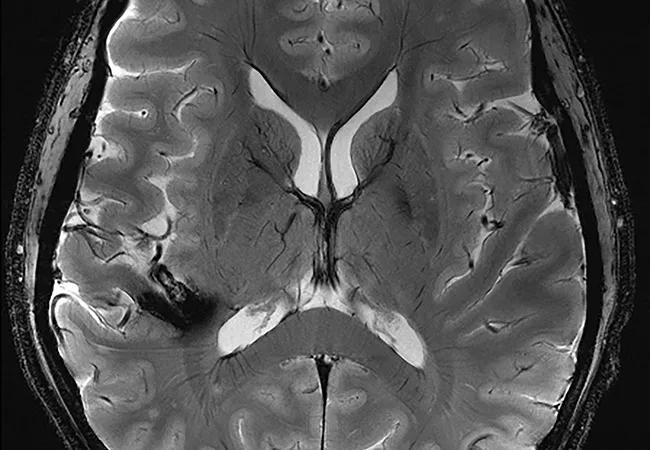

Figure. Comparative imaging studies at 3T and 7T. (A) Images of a patient with amyotrophic lateral sclerosis in which 7T reveals enhanced signal loss along the motor strip of the precentral gyrus. (B) Images of an orbital melanocytoma of the optic nerve head, with 7T clearly showing the relation of the tumor to the nerve head, an important detail for managing surgical treatment. (C) Images of a large cavernous malformation, with 7T revealing superior details of the lesion with respect to underlying anatomy. (D) Images demonstrating left frontal cortical dysplasia. Note how 7T clearly shows superior delineation of the subcortical lesion.

A conclusion appears to be emerging from these studies that 7T neuroimaging will have a future clinical impact in cases where lesion detail is important and enhanced resolution would aid diagnosis. Typically, 7T imaging does not show lesions invisible at lower field strengths but rather shows visible lesions in greater detail, which can be medically important. While the simple presence of a lesion on a study is significant, so too is the lesion’s conspicuity so that a radiologist’s eye can detect it.